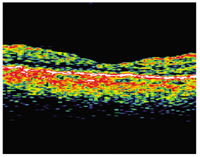

| This patient with

predominantly classic choroidal neovascularization of approximately 6 Macular Photocoagulation Study disc areas (images to the far left) had distance vision of 20/64, near vision of 20/100 and a reading speed of 109 words per minute. At 1 year after an MTS360 procedure (images to the right), distance vision was 20/40, near vision was 20/20 and reading speed was 150 words per minute. At 2 years post-op, distance vision was 20/40, near vision was 20/25 and reading was 171 words per minute. |